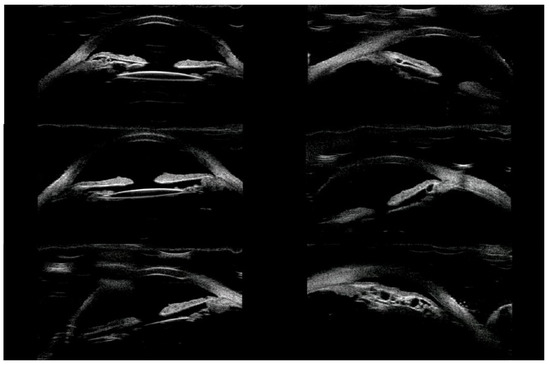

The aim of this study is to present interesting images of a clinical case of asymmetrical bilateral ciliary body cysts associated with pseudoexfoliative syndrome (PEX), leading to unilateral reverse pupillary block and subsequent secondary angle-closure glaucoma in a 64-year-old patient who presented with [...] Read more.

The aim of this study is to present interesting images of a clinical case of asymmetrical bilateral ciliary body cysts associated with pseudoexfoliative syndrome (PEX), leading to unilateral reverse pupillary block and subsequent secondary angle-closure glaucoma in a 64-year-old patient who presented with vision loss and redness, revealing angle-closure glaucoma in the left eye. Slit lamp examination showed an asymmetrical iris configuration between the eyes, with a normal appearance in the right eye and an inverted “volcano-shape” iris appearance, corresponding to reverse pupillary block, with pseudoexfoliation in the left eye. Multimodal imaging confirmed the presence of bilateral ciliary body cysts, which were unexpectedly identified in the right eye. The patient’s secondary angle-closure glaucoma in the left eye was likely due to anterior displacement of the iris from these cysts. Following an inadequate response to topical and systemic treatments, the patient underwent trabeculectomy in the left eye, successfully stabilizing the intraocular pressure (IOP) and leading to the resolution of the reverse pupillary block. This case underscores the importance of thorough ocular examination and multimodal imaging in diagnosing complex clinical presentations like secondary angle-closure glaucoma stemming from the combination of ciliary body cysts’ pressure towards the angle, the pseudoexfoliative material component, and the reverse pupillary block configuration. All of the findings provided critical diagnostic clues leading to the identification of the underlying pathology. Full article

Show Figures

Figure 1